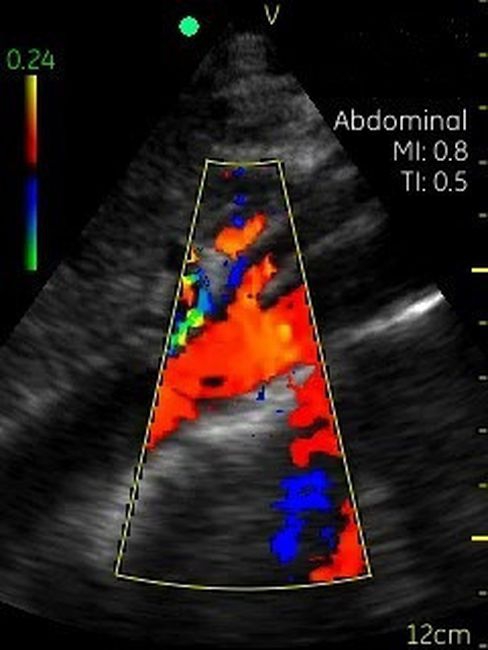

Невозможно было представить раньше, что УЗИ аппарат может помещаться на ладони руки человека. Теперь это реальность, воплощенная в корпусе и технологической начинке GE VSCAN. Инженеры заложили возможность получения дополнительной визуализации кровотока с цветной кодировкой в режиме реального времени для полноценной постановки диагноза на месте.

Визуализация Vscan:

· Наложение кровотока с цветовой кодировкой в реальном времени.

· Сектор цветного режима показывает кровоток с углом обзора 30 градусов

· Широкополосный фазированный датчик с частотой от 1,7 до 3,8 МГц.